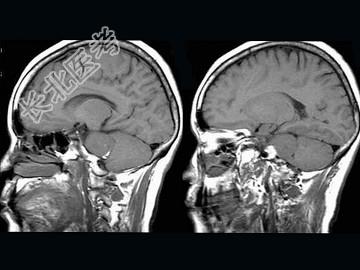

- 单项选择题女,57岁, 左侧听力进行性减退半年余,MRI检查如图, 最可能的诊断为 ( )

A、听神经瘤

B、三叉神经瘤

C、胆脂瘤

D、脑转移瘤

E、桥小脑角脑膜瘤